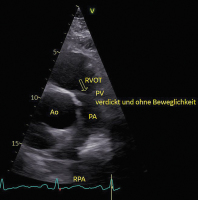

Abbildung 1: Patient mit schwerer PI bei Karzinoid (neuroendokriner TU); die PK-Taschen (Pfeil: die Taschen sind nur schwer zu sehen) sind überall verdickt und unbeweglich. Bei einer postrheumatischen PI/PS wären nur die Spitzen verkalkt.